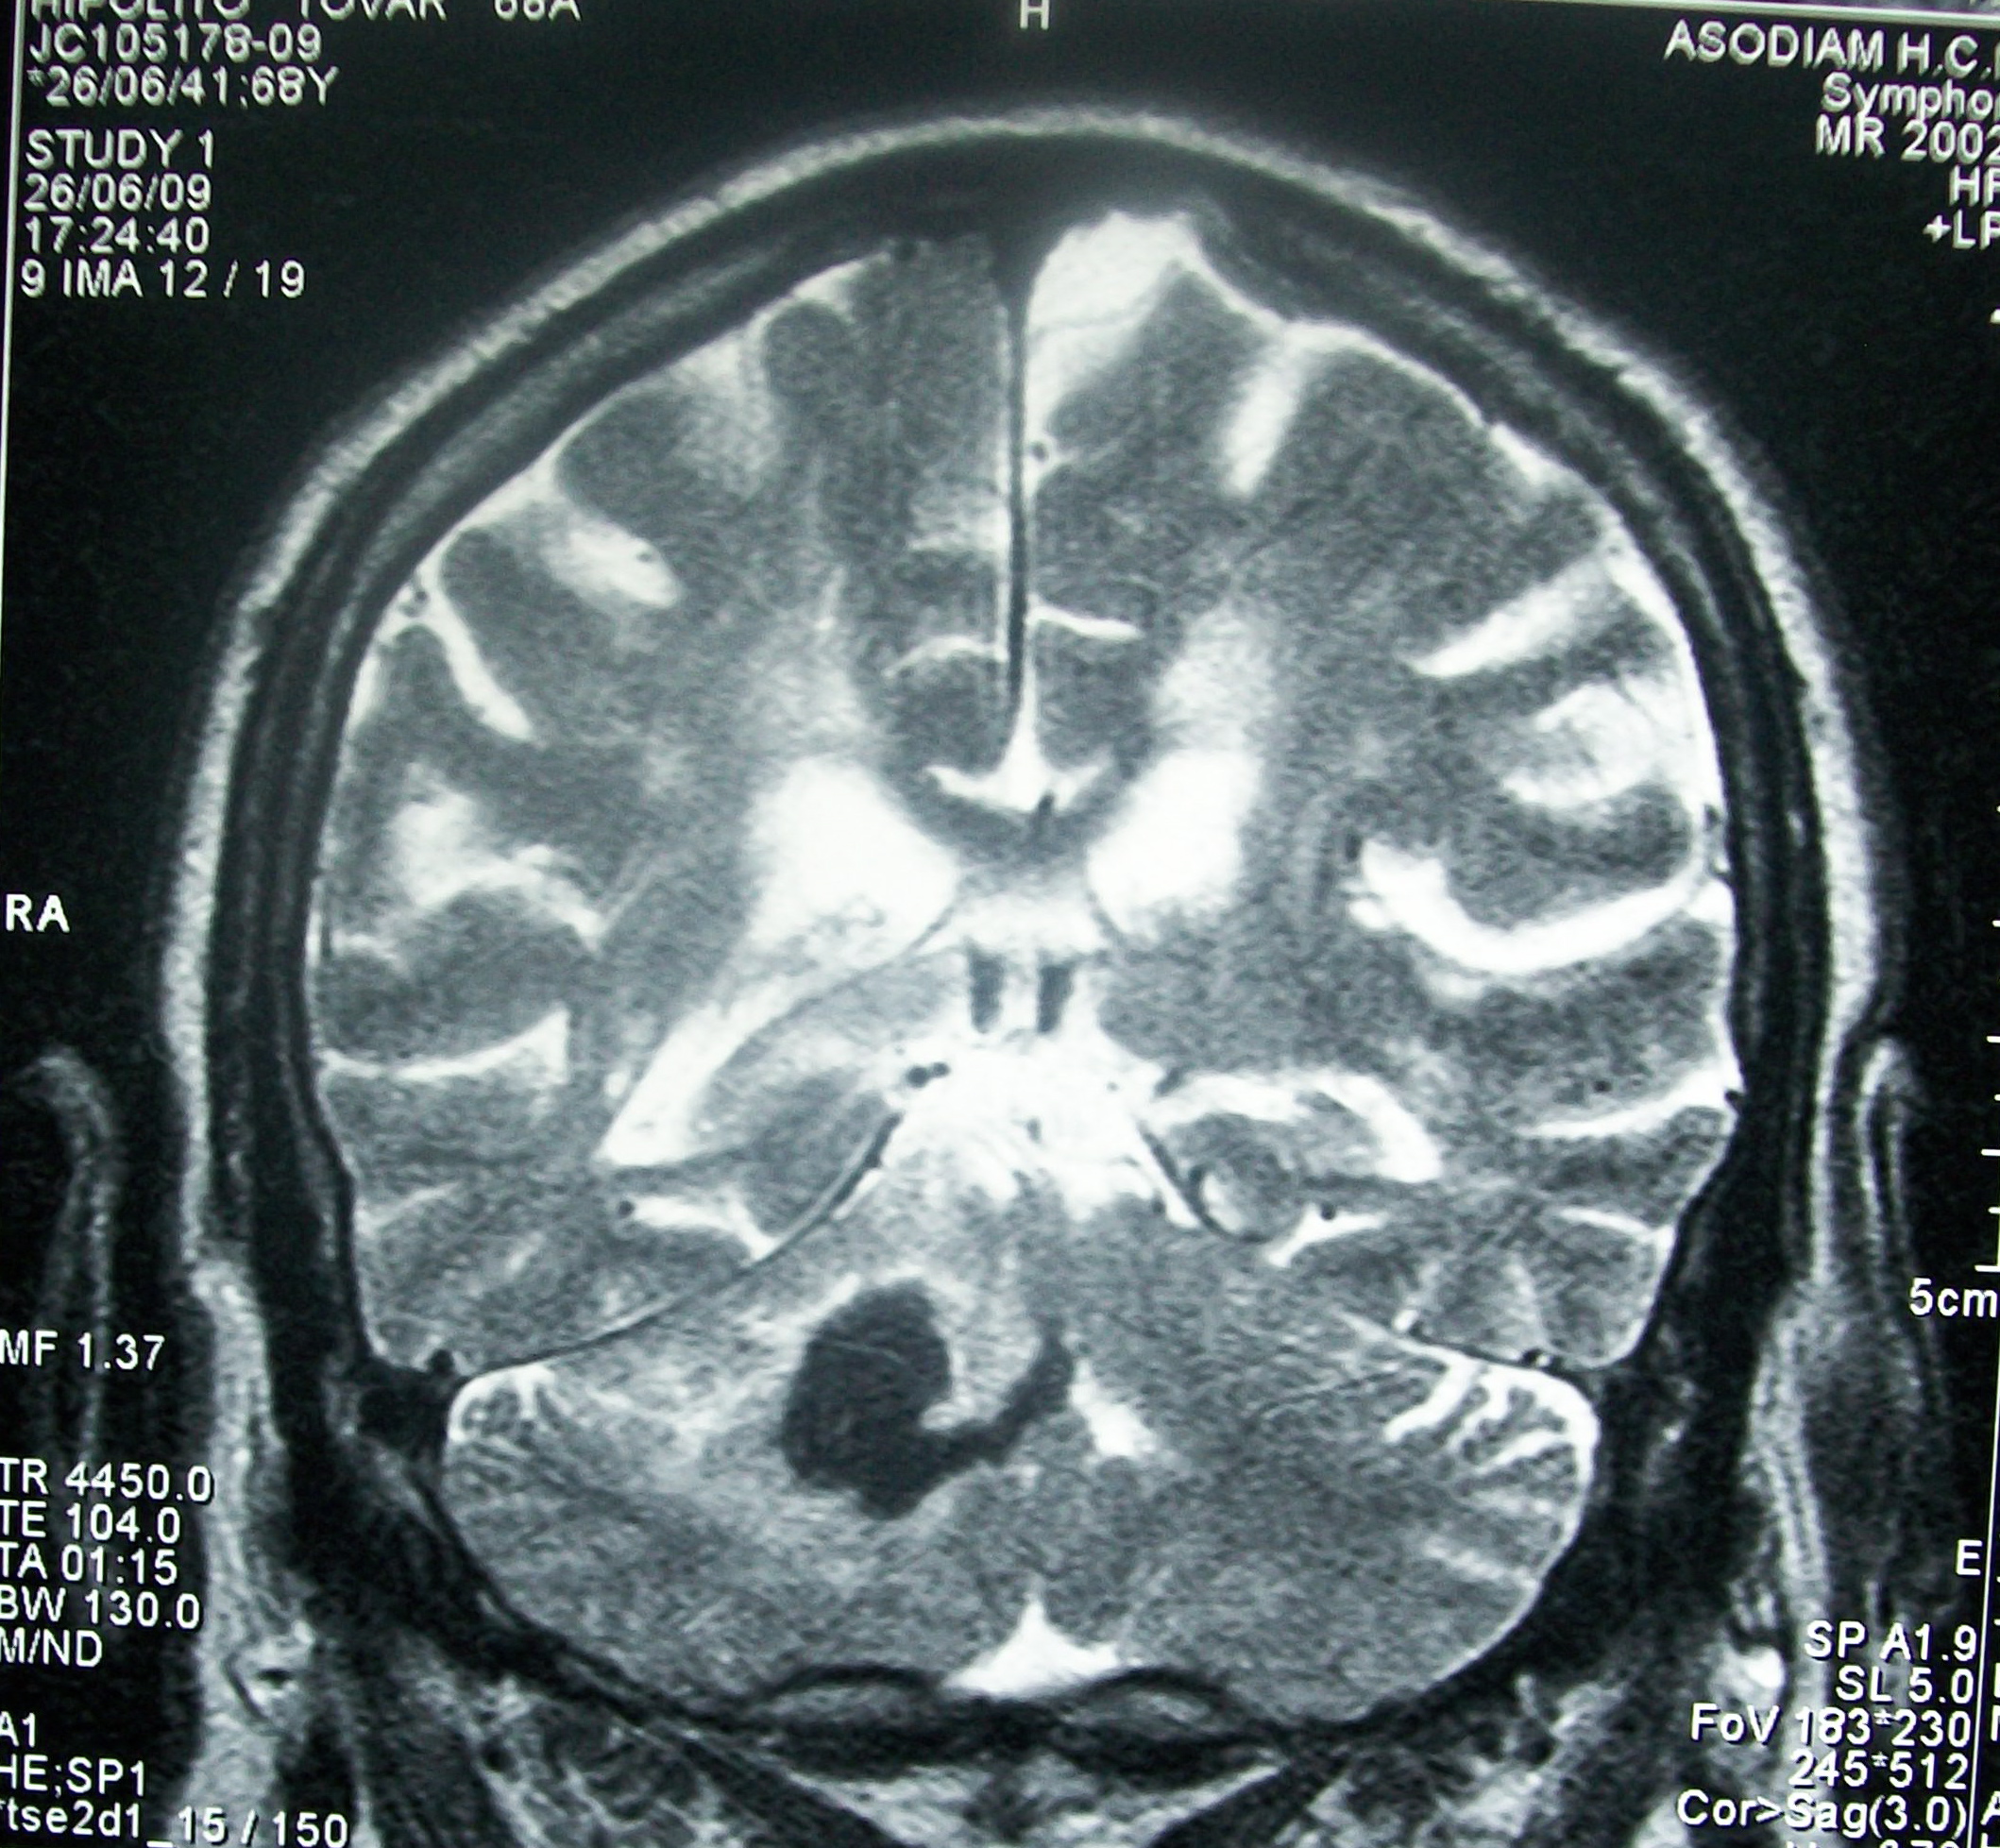

Having a stroke inflicts several problems on the human body that, if left untreated, could significantly impair normal functions. One of the worst effects of a stroke includes damage to brain cells, which can lead to permanent mobility issues. Thanks to a newly developed drug, the damage caused by a stroke to the brain could be mitigated and can even help repair damaged cells.

The new drug in question is interleukin-1 receptor antagonist (IL-1Ra) and was developed by The University of Manchester researchers, which addresses the damage caused by stroke due to the reduction of blood flowing to the brain, MedicalXpress reports. Due to stroke cutting off blood flow to the brain, oxygen deprivation would set in, which is what kills brains cells that then lead to disabilities and even death.

By promoting neurogenesis, which is basically a means of healing damaged brains cells, the new drug that the researchers created is able to help treat the damage that previous stroke incidents induced. The double benefits have staggering implications for stroke victims, largely because it means that even those who already experienced the health episode can still take advantage of the new drug.